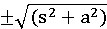

- доза, вызывающая гибель 50% животных

- доза, вызывающая гибель 50% животных